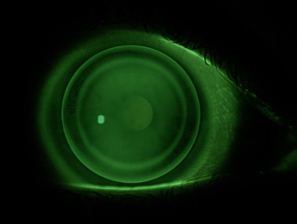

In het fluobeeld is een juiste passing van een Comfort lens te zien met een gelijkmatige fluo-verdeling en rondom een kleine edge lift. De reservoir-zone is normaal zichtbaar, de centratie is perfect.